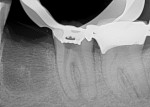

Even a seemingly well-completed root canal treatment (RCT) can fail if all of the pulpal tissue is not fully removed. In this case, the GentleWave® Procedure (Sonendo, Inc., gentlewave.com/doctor) was used to successfully retreat a failing traditional RCT. The GentleWave System is the first and only FDA-cleared system for RCT that addresses the limitations of conventional methods by combining procedure fluid optimization, broad-spectrum acoustic energy, and advanced fluid dynamics to debride and disinfect deep regions of the complex root canal system in a less-invasive procedure that preserves tooth structure. Tooth No. 19 was removed due to a fractured root prior to retreatment of tooth No. 18. The patient was administered anesthetic, and a rubber dam was placed for isolation. A conservative removal of the existing gutta-percha was accomplished using minimal rotary files. A SoundSeal® platform was constructed onto the tooth and treated with a CleanFlow™ procedure instrument (PI). The CleanFlow Technology cleans and disinfects without the PI entering the tooth. After 8 minutes and 15 seconds, the CleanFlow PI was removed and the canals dried. The molar system was filled to complete the retreatment in a single visit. Postoperative 2D and 3D radiographs demonstrated outstanding apical results. At the 1-month follow-up appointment, the patient reported no postoperative pain.